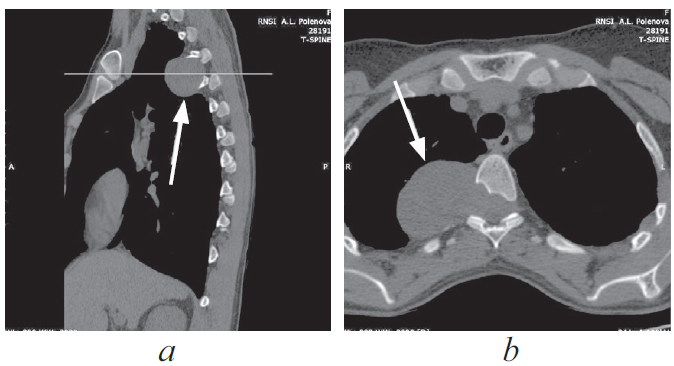

С целью оценки положения опухоли относительно окружающих костных структур была выполнена многослойная компьютерная томография грудного отдела позвоночника, по данным которой в проекции расширенного правого межпозвонкового отверстия Тh-Тh5 выявлено солидное объемное образование с четкими контурами, размерами 38,7 × 1,9 × 51,1 мм, распространяющееся паравертебрально вправо, правые отделы позвоночного канала деформированы, имеется экскавация заднеправых отделов тела позвонка Тh и правой дужки (рис. 3).

Рис. 3. Многослойная компьютерная томография грудного отдела позвоночника, сагиттальная (а) и аксиальная (b) проекции. Опухоль указана стрелками, визуализируется экскавация заднеправых отделов тела позвонка Тh и правой дуги

Fig. 3. MSCT of the thoracic spine, sagittal (a) and axial (b) projection. The tumor is indicated by arrows, the excavation of the posterior-right parts of the Th vertebral body and the right arch is visualized

По классификации Eden — тип IV, по классификации Sridhar — тип IVb [3, 9].